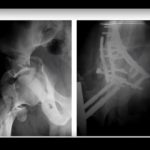

Courtesy: Prof Cyril Mauffrey, FRCSOrth, Denver